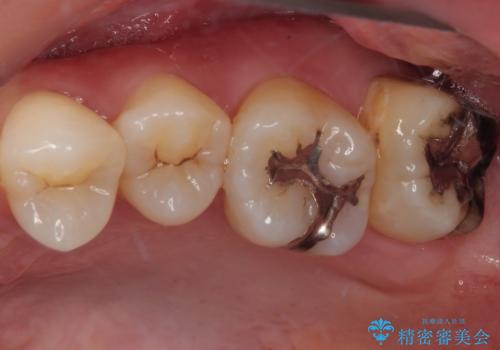

- 元々むし歯があったものの、処置が困難とのことでしたが、矯正治療を終えたので処置をしたいとのことで来院された患者様です。

左右ともに最後臼歯が頬側に顕著に突出しており、むし歯になってしまったことが想像されました。

歯列が移動したとはいえ、左右ともに後方傾斜しており、むし歯の除去、形成(形を整える)、型取りの全てが非常に困難な処置となりました。